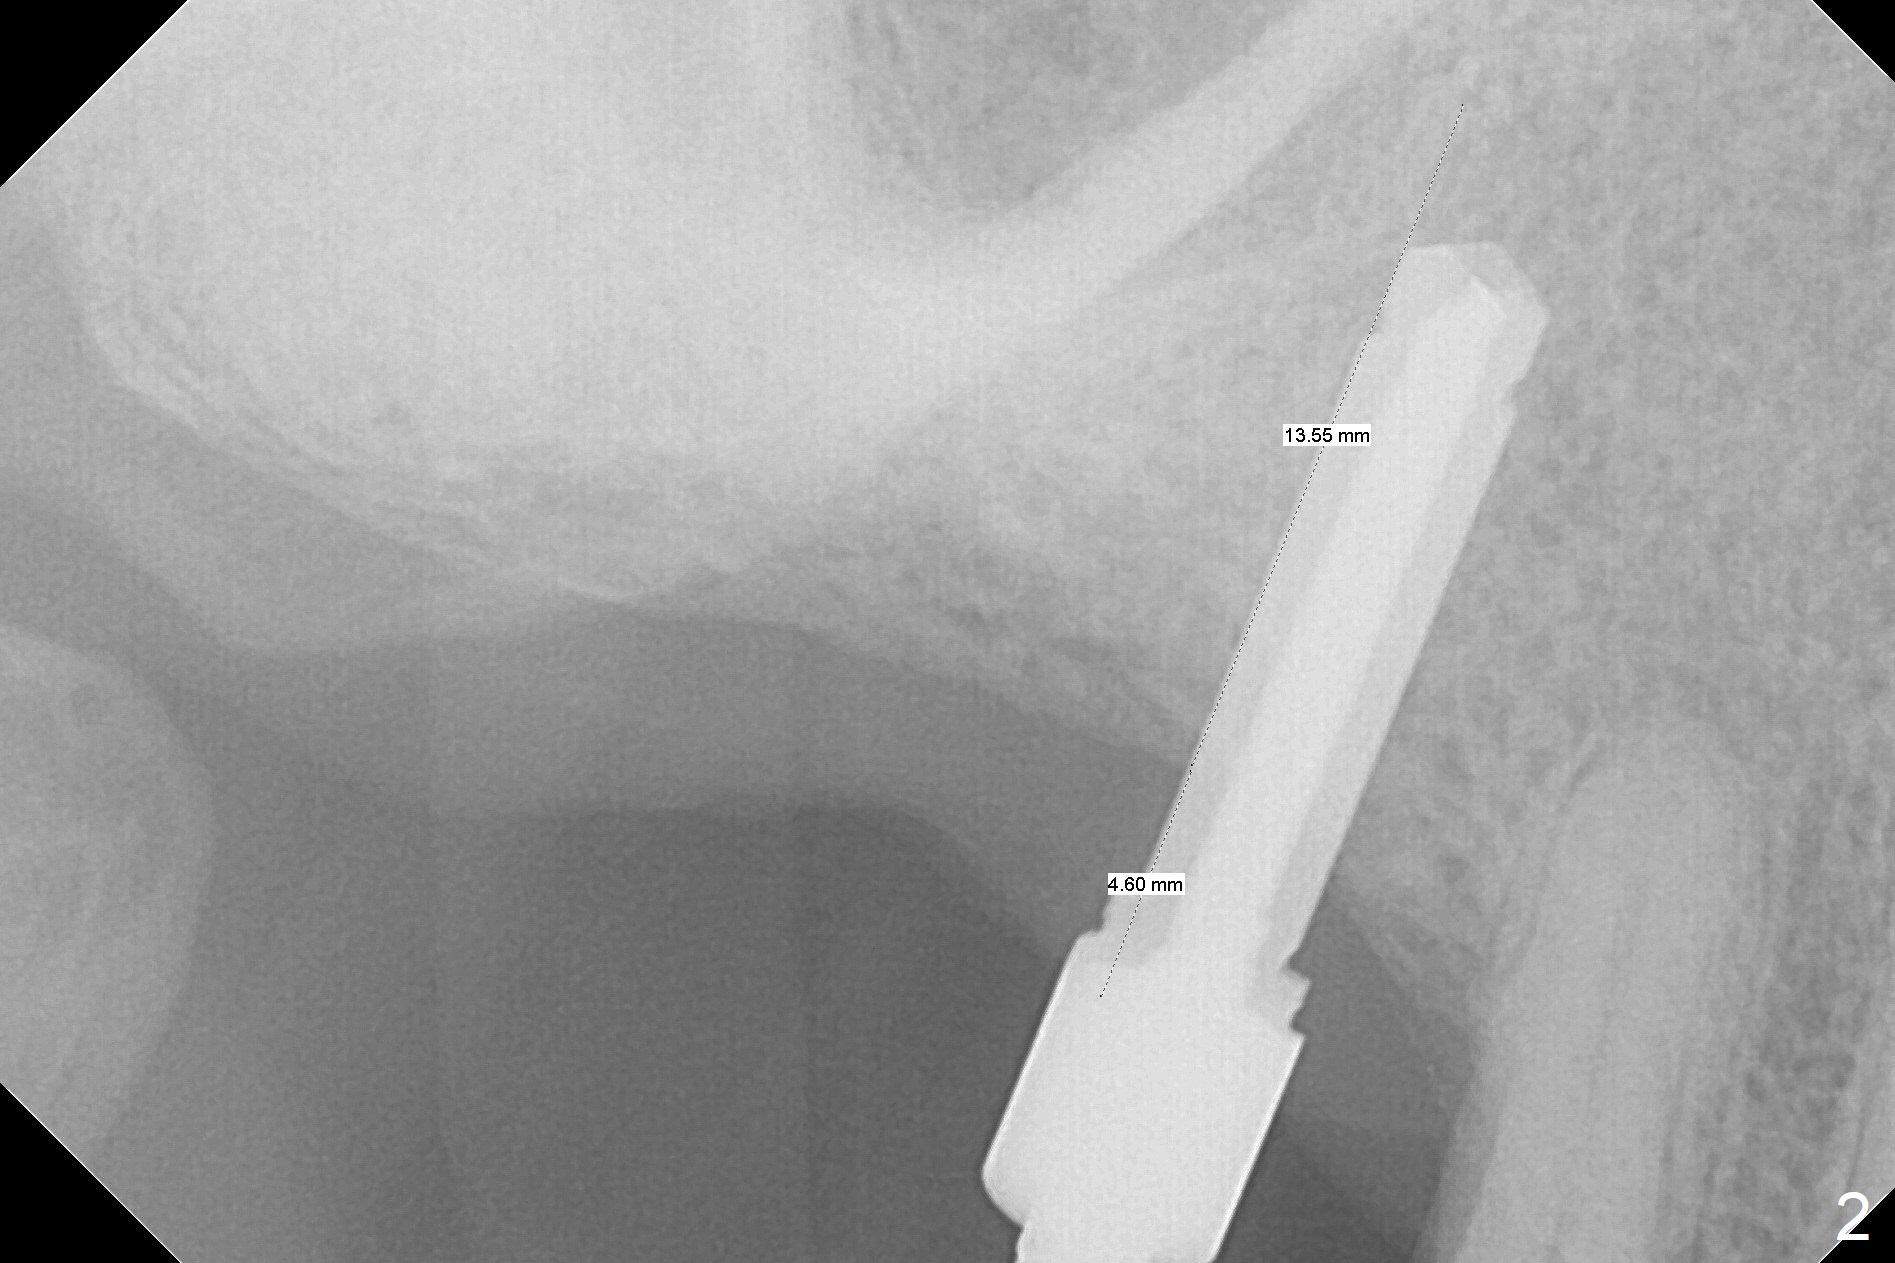

Since the ridge crest at #3 is narrow, Tatum bone scalpels are used to get access and initiate bone expansion, followed by bone blades and RT 2. It seems that the osteotomy starts mesially; bone height being increased (Fig.1). When the apical end of the osteotomy tilts mesially, more bone height is obtained. Drills are alternatively applied because of the hard bone (Fig.2). A 4x13 mm UF implant is placed initially with the distal threads unburied (Fig.3, >50 Ncm). With further seating of the implant, a 5.5x5(4) mm abutment is used (Fig.4), which closes the access. No suture is warranted. An immediate provisional is fabricated for the patient's comfort and psychological effect. In fact, the abutment cuff changes to 5 mm prior to temporarization. There appears no bone loss <4 months postop (Fig.5). Pulpitis develops at #4 due to DO caries 1 year 5 months post cementation (Fig.6 *). The crown at #3 is removed for easy and conservative distal carious removal and Cavit temporary restoration to prevent sodium hypochlorite leakage. Then occlusal access is made for pulpotomy. When RCT finishes, no crown will be made, but occlusal reduction is required. The patient returns for RCT 1 month later (Fig.7,8). Cavit remains in place (Fig.7 C). Although 2 threads are exposed distal (Fig.8 arrow), there is no sign or symptom of periimplantitis, which may be related to the thick gingiva (arrowhead). Return to Upper Molar Immediate Implant, IBS, #14 (Tissue Punch) Xin Wei, DDS, PhD, MS 1st edition 08/25/2017, last revision 09/08/2019